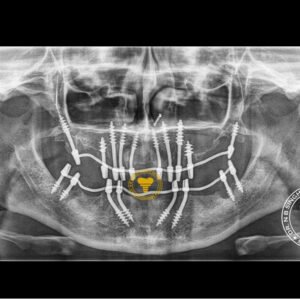

1002 Basal Full Mouth Implants Case Rubeena 2

1002 basal implant full mouth case rub 4